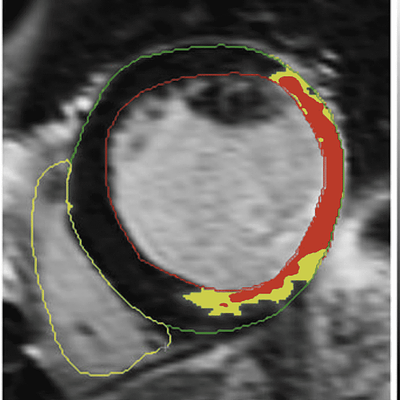

The preprocessing steps. Left Definition of the contours, Middle Definition of scar (gray zone (in yellow) and core zone (in red)) and Right The composition of the mesh based on the contours in 3D. The last described preprocessing step of indicating the position of the origin of the left main coronary artery is not included in this figure

Corine Godeschalk-Slagboom, Rob van der Geest, Katja Zeppenfeld, and Charl P. Botha

International Journal of Computer Assisted Radiology and Surgery, 2012